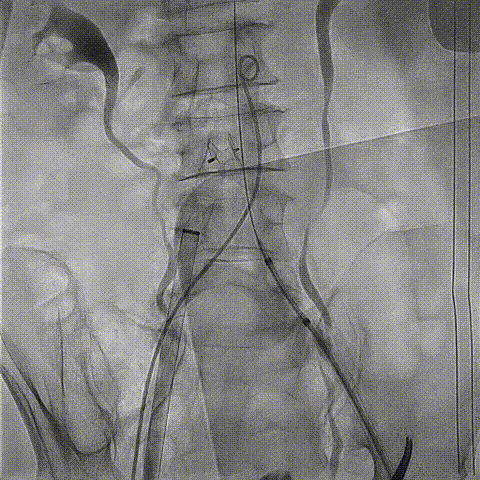

术中全麻、气管插管,穿刺双侧股动脉及股静脉。经右侧颈内静脉置入中心静脉导管,经左侧桡动脉置入动脉测压导管,经右锁骨下静脉置入临时起搏器。经右股静脉置入7F JR指引导管至下腔静脉,经右股动脉置入6F猪尾导管至腹主动脉,于下腔静脉及腹主动脉同时造影精确定位目标穿刺点。

下腔静脉及腹主动脉同步造影确定穿刺点

经右股静脉内的7F JR指引导管联合Finecross微导管及Conquest pro导丝构成穿刺系统,外接电刀,导丝顺利穿透腔静脉壁、腹主动脉壁达腹主动脉内。送入Finesross微导管至腹主动脉后,交换Conquest pro导丝为BMW导丝至升主动脉,圈套器抓捕BMW导丝头端建立腔静脉至腹主动脉通路。

穿刺系统与圈套器配合完成穿刺并建立下腔静脉至腹主动脉的通路